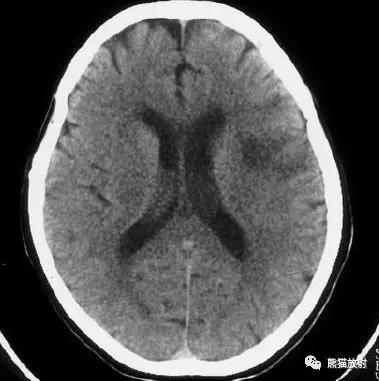

左侧大脑中动脉区域大面积梗死,明显不均质强化。

右侧大脑中动脉区域脑梗死,脑回样强化。

左侧额叶脑梗死(发病后12d),由于模糊效应平扫显示不清,增强扫描脑回样强化。